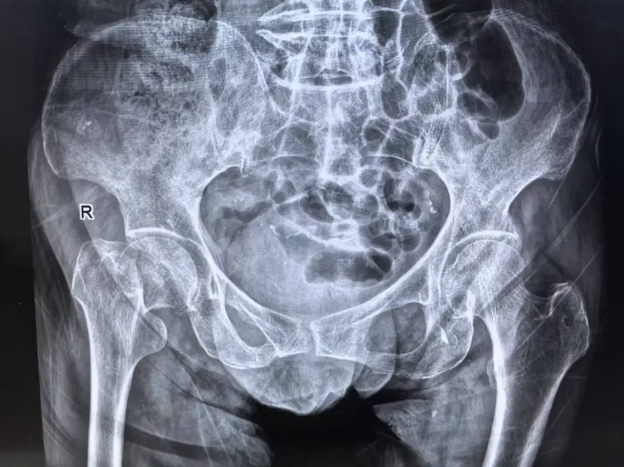

此前,91歲的肖奶奶失衡跌倒,家屬憂心忡忡求助洛陽新里程醫(yī)院骨科。入院后,經(jīng)全面影像顯示右側(cè)股骨頸骨折,伴肺氣腫、慢支、冠狀動脈粥樣硬化等多種基礎疾病。這個被骨科界稱為"銀發(fā)殺手"的髖關節(jié)骨折損傷,正悄然吞噬著老人的生存希望。

右側(cè)股骨頸骨折